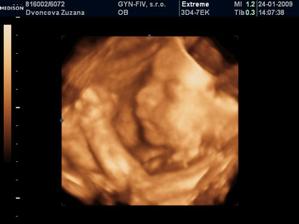

24.1.2009 nám pán doktor prezradil na 3D, že čakáme chlapčeka :o) ....po dlhom rozhodovani sme si povedali, ze to bude maly Nicolas...uz sa velmi tesime, ked pride na svet...caka ho tu cela velka rodina, ktora ho uz teraz velmi lubi :o))